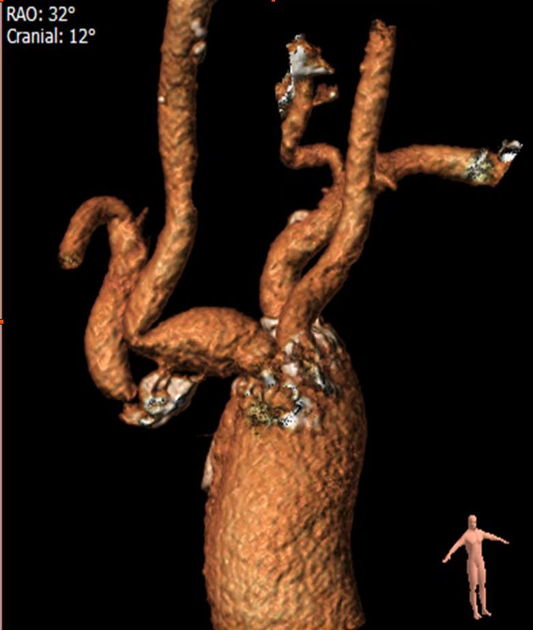

复杂的右锁骨下动脉闭塞病变:

对于闭塞病变,开通导丝的方向至关重要。根据CTA提示的特定角度(如 RAO 32° CRA 12°)进行投照,能为术者提供最清晰的路径导向,成功引导导丝通过闭塞段。

图:CTA提示 RAO 32  CRA 12

图:按RAO 32  CRA 12开通成功